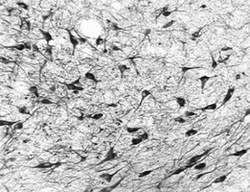

Supportive validation

- Submitted by

- OriGene (provider)

- Main image

- Experimental details

- Immunohistochemistry-frozen: Ogg1 antibody - Detection of OGG1 in formaldehyde fixed frozen sections of the substantia nigra from a Rhesus macaque (Macaca mulatta) using anti-OGG1 at 10 ug/ml. Photo courtesy of Glen Kisby, Oregon Health Sciences University. The tissue was a generous gift of Dr. Steven Kohama, Oregon National Primate Research Center.

- Validation comment

- IHC